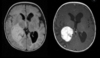

Linfoma SNC Tumor infiltrativo, supratentorial, atravessa a linha média Acomete a profundidade dos hemisférios cerebrais Realce intenso sólido, sem necrose Restrição a difusão Hiposinal T2

LINFOMA PRIMÁRIO DO SNC: 90% supratentoriais; Geralmente linfoma não hodgkin (celulas b); localização periventricular e nucleos da base; pode atravessar linha média (corpo caloso); TC: iso / hiperdensa com realce pos contraste; pode haver necrose; RM: Hipossinal em T1 e T2 com forte realce homogêneo pós contraste (realce anelar em imunossuprimidos); restrição a difusão;